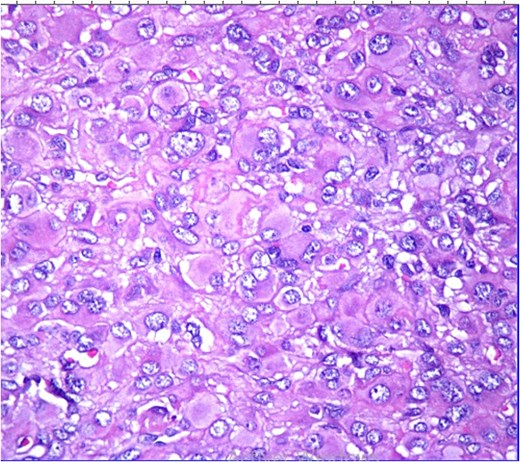

Histopathological analysis revealed a poorly differentiated dermal neoplasm arranged in a solid growth pattern. The tumor cells were epithelioid, with abundant eosinophilic cytoplasm and centrally or eccentrically placed nuclei exhibiting moderate atypia and prominent nucleoli (Figs 1 and 2). The mitotic rate was 4 per 10 high-power fields (HPF). The stroma was fibrous, and the surgical margins were involved. Immunohistochemical analysis showed tumor cells positive for vimentin, CK7, and S100 protein, with a MIB-1 proliferation index of 5%. Negative staining for cytokeratin, androgen receptors, PHLDA1, and p63 excluded adnexal tumors. Additionally, vascular markers (CD34, CD31, ERG), muscular markers (desmin, caldesmon, actin, myogenin), histiocytic markers (CD68, CD163, MMP11), plasmacytic markers (CD138, MUM1), and melanocytic markers (Melan-A, HMB45) were negative.

HE ×20: A diffuse poorly differentiated neoplasm composed of pleomorphic epithelioid cells.